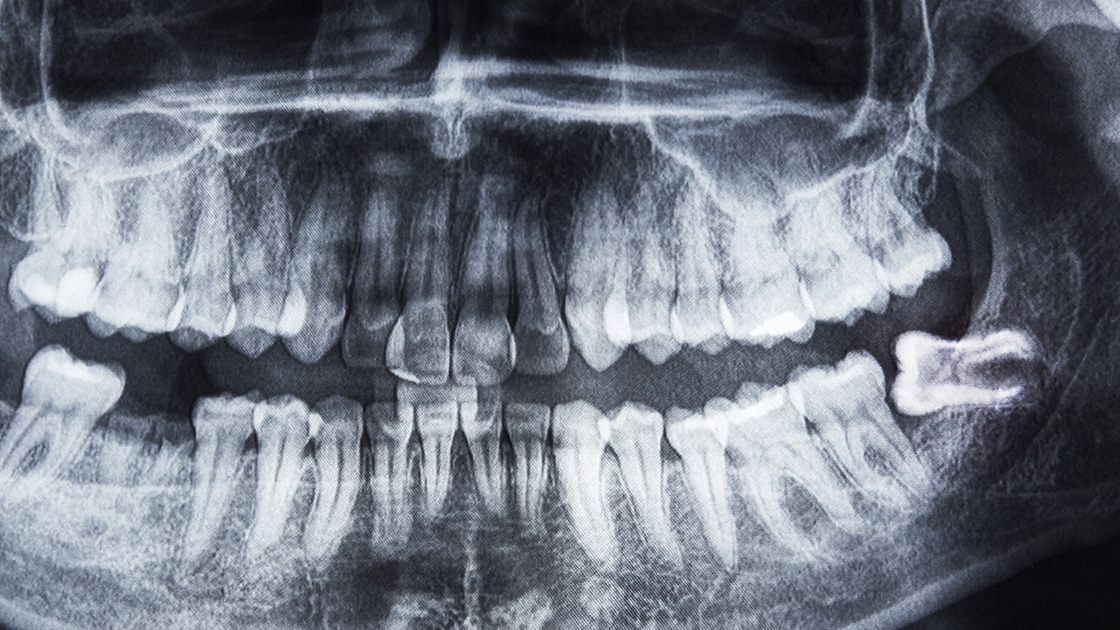

An impacted tooth is one that is blocked from erupting. Impacted wisdom teeth that are blocked from coming in properly:

May instead come in at an angle, pushing against the molars and causing overcrowding.

May not erupt fully, remaining instead either partially or fully below the gum line.